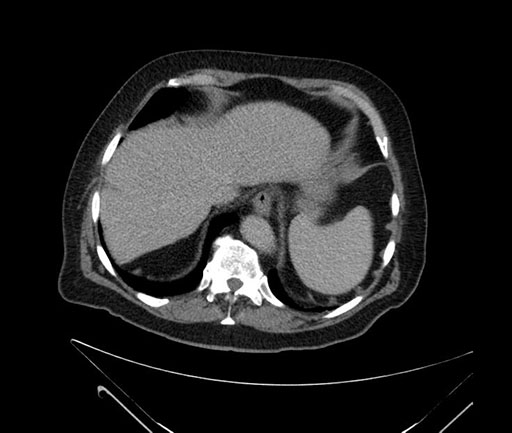

Whipple (pancreaticoduodenectomy) [case 7]

Imaging Analysis

Look through the patient's CT scan to identify any areas of concern for the necessary procedure.

Based on your CT findings, which issue(s) would give reason for "planned slowing down moment(s)" in this case?

Considering a standard Whipple procedure, what step(s) of the operation would you do differently in this case?